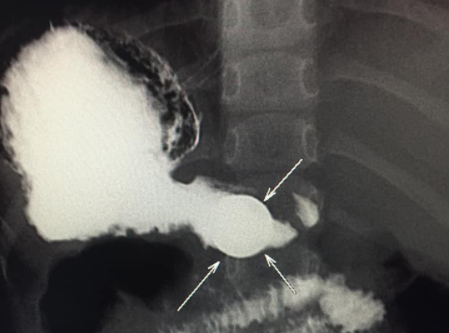

"Bir həftə qabaq 4 yaşında uşaq 5 qəpik udub. Bir həftədir qəpik uşağın mədəsindən ifraz olunmur. Gətiriblər müayinəyə, biz də aşkar etdik ki, qəpik hələ mədədir. Mədənin çıxacaq hissəsi uşaqlarda dar olduğuna görə çıxmır. Qəpiyin diametri mədənin çıxacaq hissəsinin diametrindən iki dəfədən çox böyükdür. Ona görə mədədən keçmədi, qalıb mədədə. Biz məsləhət gördük ki, endoskopiya müayinəsindən keçsin, endoskopik yolla çıxartsınlar. Hələ bir xəbər yoxdur. Qəpik uşağın mədəsindən çıxarılacaq".